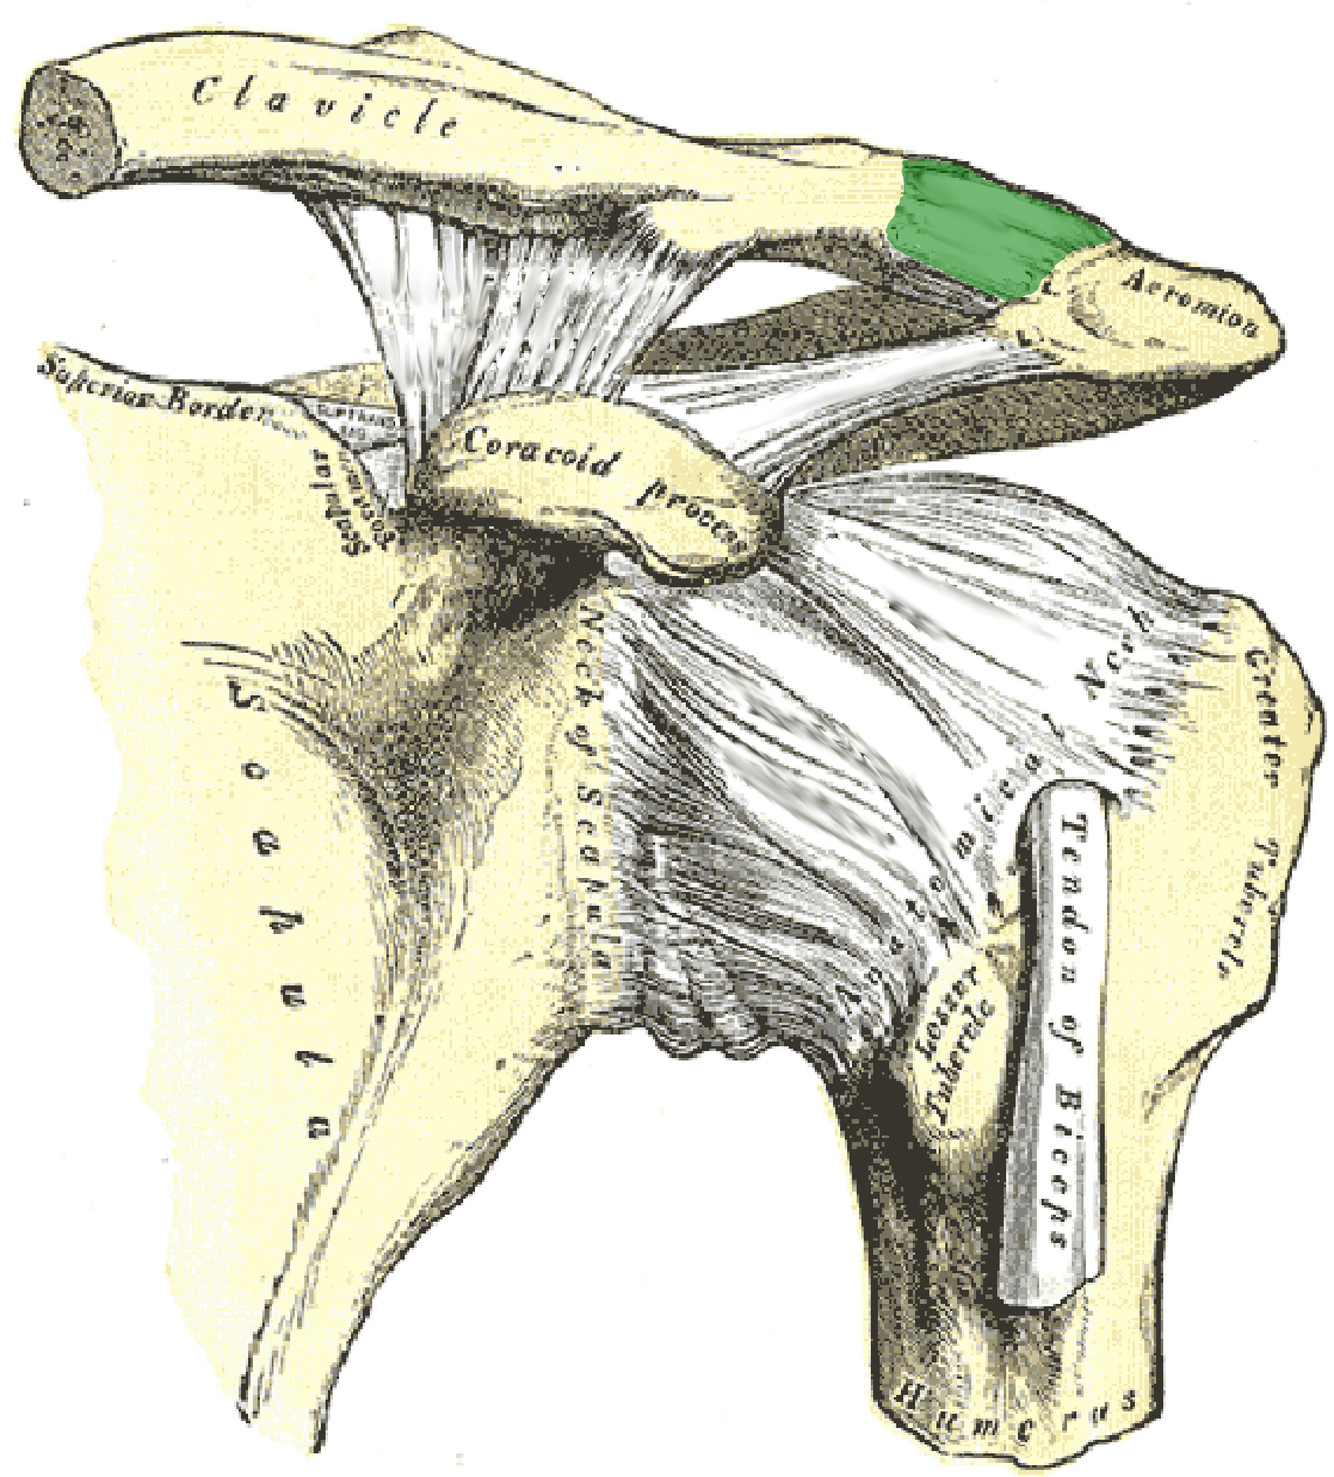

What is this structure?

Acromoclavicular ligament of the shoulder